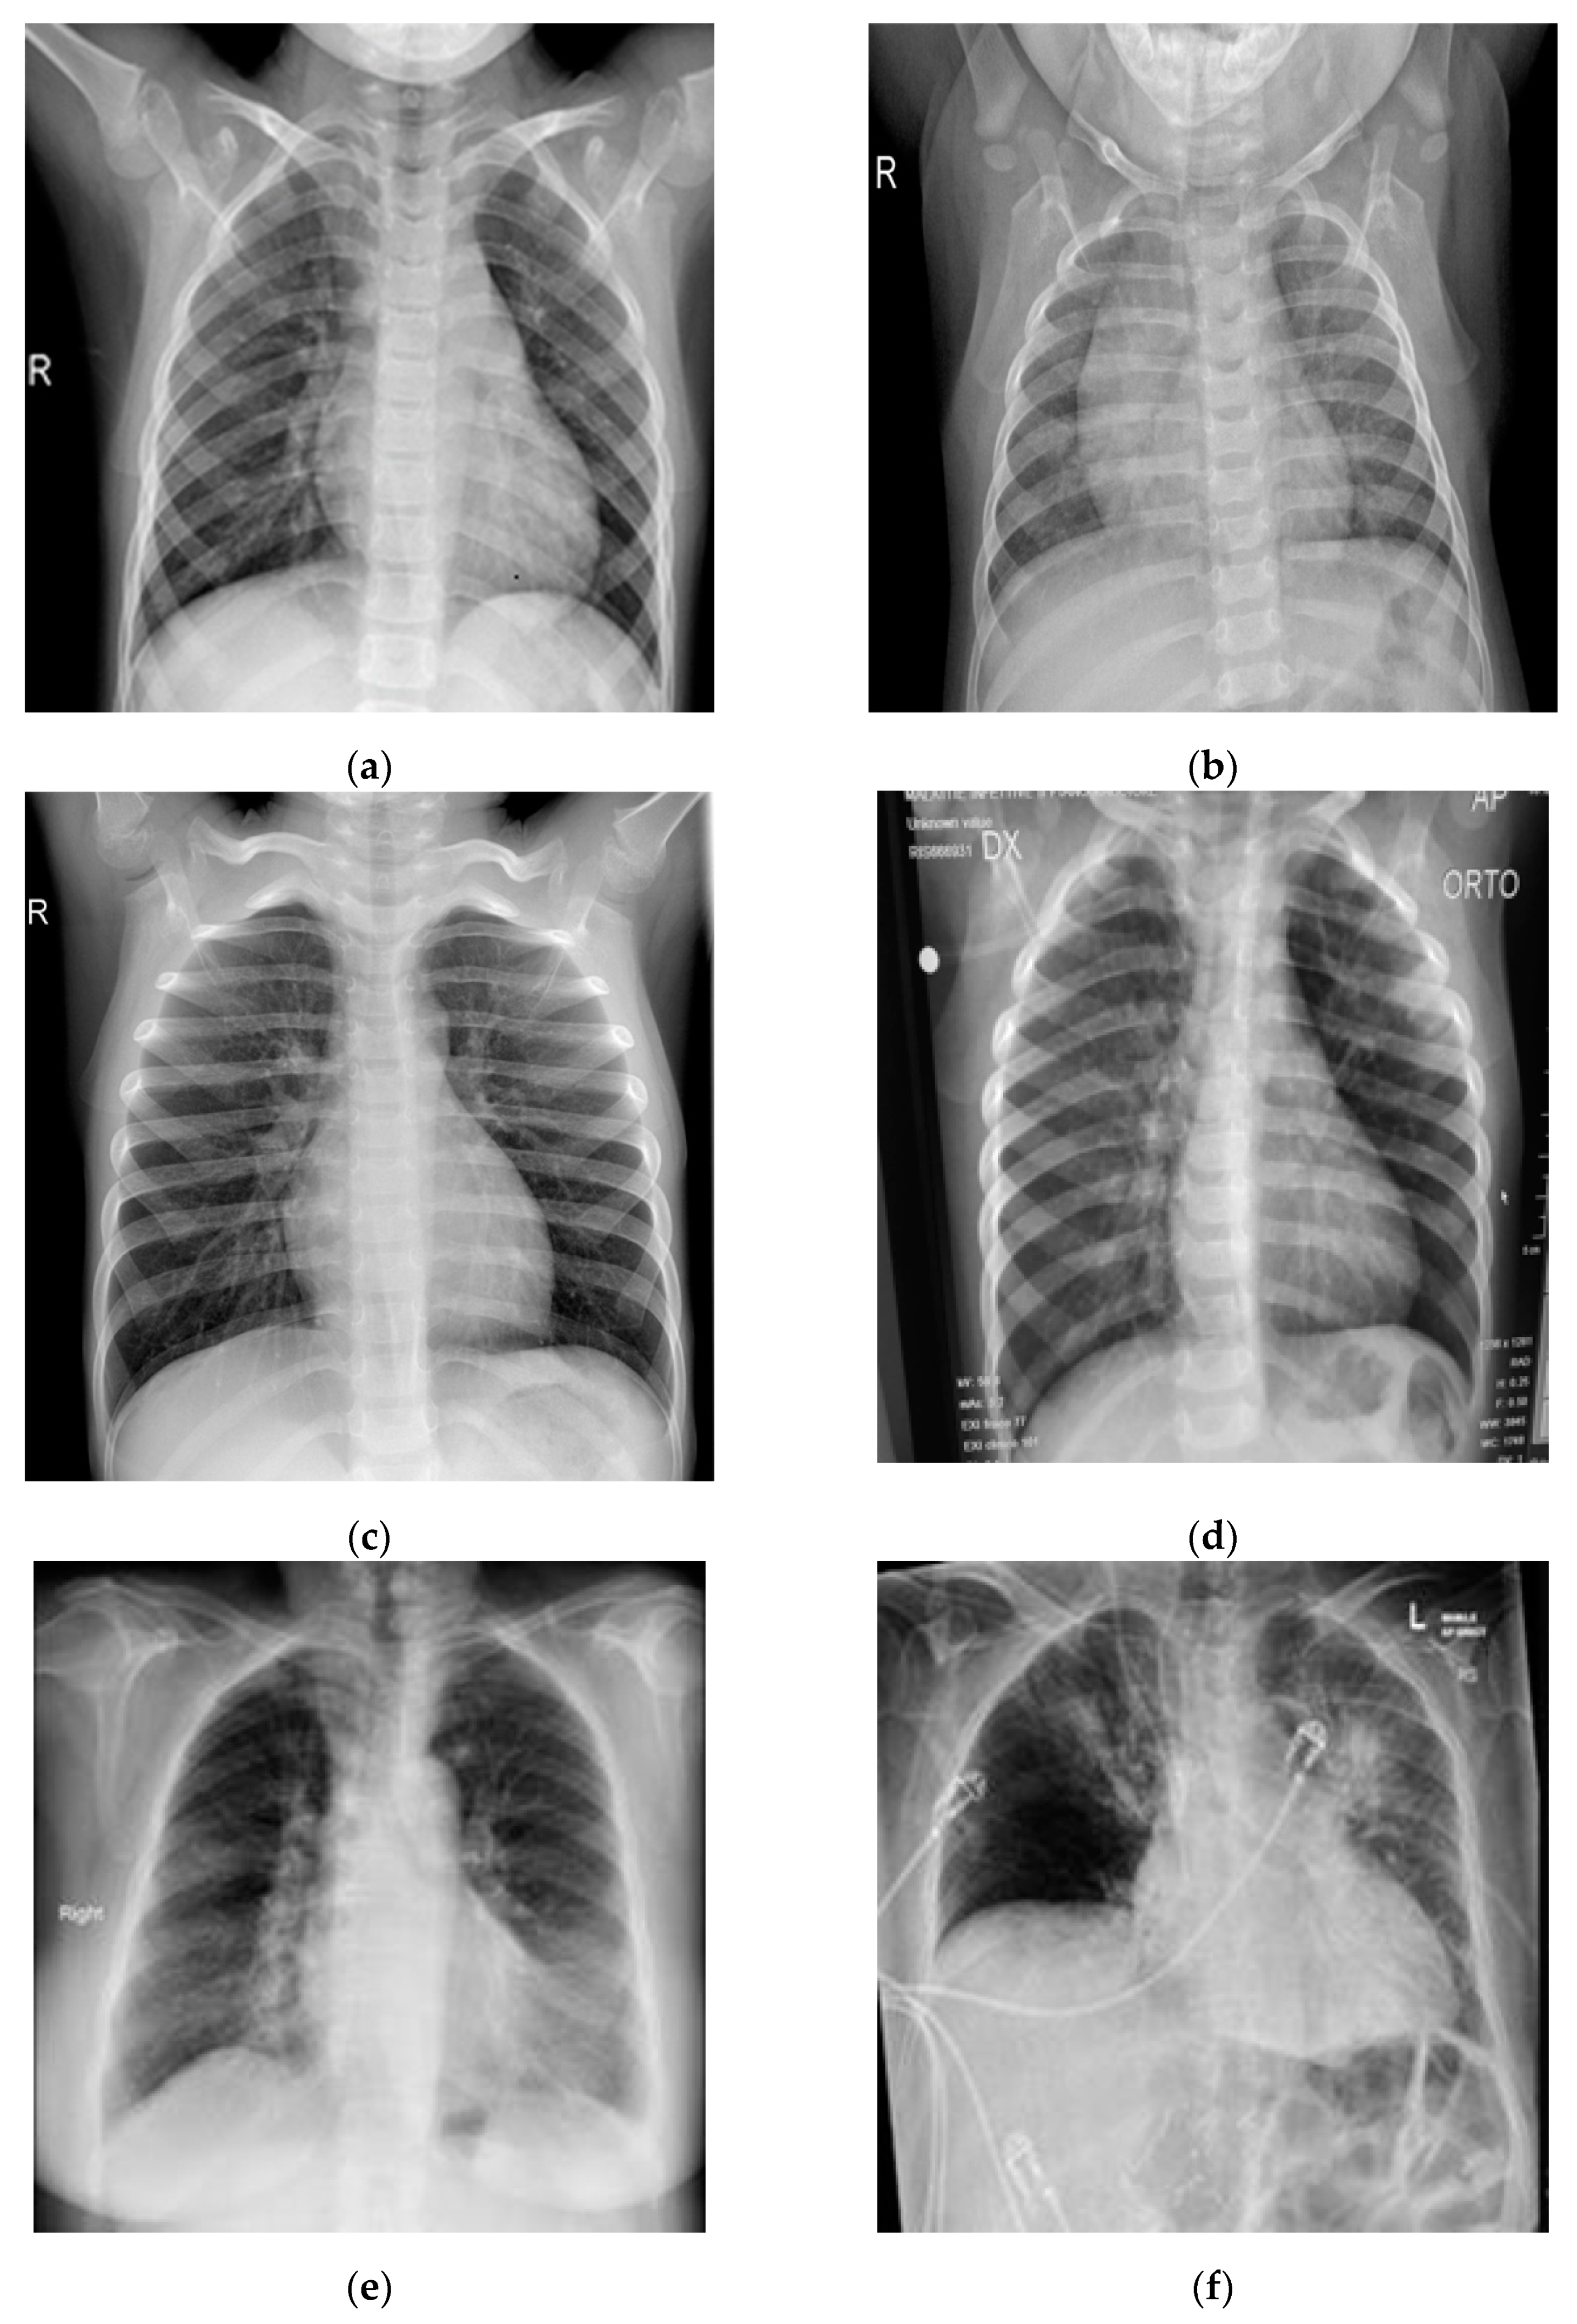

In this study, pulmonary (chest) X-ray images were used for the diagnosis of COVID-19. The dataset was categorized into two main classes, i.e., COVID-19 and normal. A total of 7232 images (3616 COVID-19 + 3616 normal) were accessed from the ‘COVID-19 Radiography Database (available at Kaggle, https://www.kaggle.com/tawsifurrahman/covid19-radiography-database, accessed on 4 May 2021) [30]. From the total images, 70% (5062 images) were used for training + validation, and the remaining 30% (2170 images) were used for testing purposes. The training + validation dataset of 5062 images was further split into a 70:30 ratio, i.e., 3544 (70%) images for training purposes and 1518 (30%) images for validation purposes. The details of the data splitting are given in Table 1. In addition to the dataset accessed via Kaggle, another locally collected dataset of 450 images (COVID-19 + normal) was also used for testing and prediction purposes. This indigenous data of chest X-ray images of Pakistani COVID-19 positive and normal patients have been collected from a local hospital. The samples of normal and COVID-19 X-ray images assessed via the Kaggle database are shown in Figure 1, whereas the samples of the locally collected images are given in Figure 2.

Figure 1.

Samples of chest X-ray images assessed via Kaggle database [30,31,32] for training purposes: (a–c) normal chest X-rays; (d–f) COVID-19 chest X-rays.

Figure 2.

Samples of local Pakistani verified dataset used for the testing of trained models: (a–c) COVID-19 chest X-rays; (d–f) normal chest X-rays.